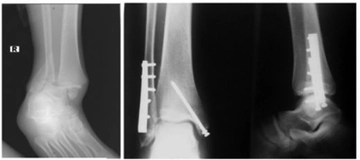

Bu yöntemler, kalça kırığının tam yerini ve türünü belirlemek için kritik öneme sahiptir. Tedavi YöntemleriKalça kırığının tedavisi, kırığın tipi, hastanın yaşı ve genel sağlık durumu gibi faktörlere bağlı olarak değişiklik gösterir. Genel olarak kullanılan tedavi yöntemleri şunlardır: